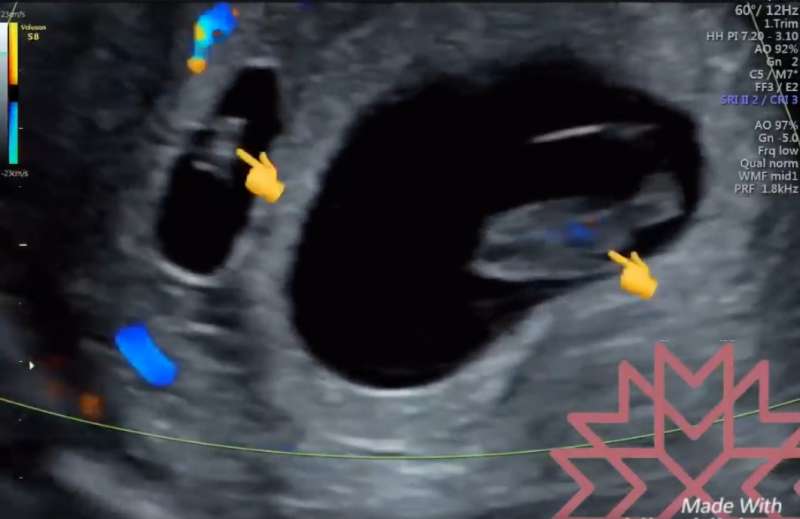

▼原來有一名孕婦來做8週的產檢時,蘇醫師突然發現在原本8週大的胎兒旁邊,出現了另一個只有6週的胚胎,兩者的頭臀圍差了2公分,是一對分別在兩週間先後著床的雙胞胎,讓他忍不住懷疑自己看錯了。

▼蘇醫師在臉書上表示:「理論上幾乎不太可能發生間隔兩周各排一次卵的事情,很複雜,在生理期荷爾蒙調控的機轉上,這真的很難發生,但它就是發生了啊」!